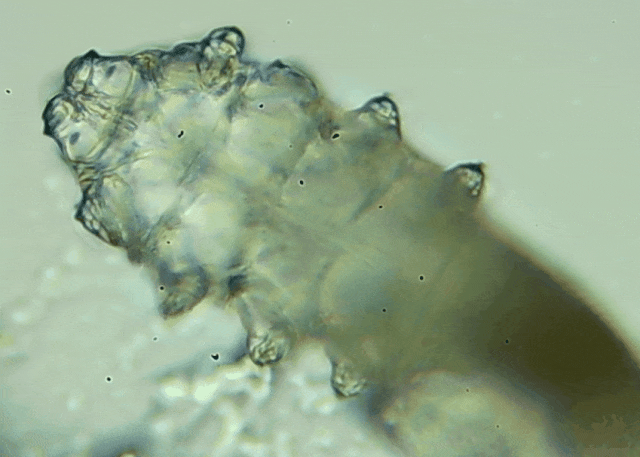

蠕形螨是一類肉眼看不見的寄生螨,常見的有毛囊蠕形螨和皮脂蠕形螨,常駐在人類的毛囊和皮脂腺里,尤其是眼睛的瞼板腺和睫毛根部。數(shù)量少時,蠕形螨能與人體“和平共處”,但一旦你免疫力下降、油脂分泌旺盛或清潔不到位,他們就會以你難以想象的速度瘋狂繁殖。

操作:醫(yī)生會在每只眼睛的上下眼瞼各拔3根典型睫毛,置于光學(xué)顯微鏡下觀察。報告解讀:任一眼瞼螨蟲數(shù)量≥3 條 →陽性,需要干預(yù)。優(yōu)勢:無創(chuàng)、快速、直觀;當(dāng)場給你看“活的”螨蟲在睫毛上爬,視覺沖擊堪比大片。